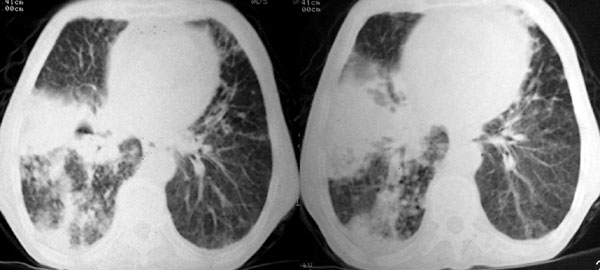

f 76 间断咳嗽 咳痰1年余 发热不明显 身体削瘦

3、右侧胸膜增厚粘连,胸腔少量积液征像;

1、右侧中央型(空洞性)肺癌并双肺受累(包括转移、阻塞性炎症、癌性淋巴管炎);纵隔、右侧腋窝内淋巴结肿大、转移;右侧胸膜增厚粘连,胸腔少量积液;

1、两肺结核,并右肺下叶干酪性肺炎及空洞形成,建议支气管镜检查,除外新生物。

3、右侧胸膜肥厚、粘连。

诊断意见:1、右侧中央型肺癌并肺内胸膜转移;2、双肺广泛间质纤维化。

病例隔的太久了,今天打开后在没有看结果之前,浏览着图片感觉象是结核,完全否定了自己以前的诊断。然后又是楼主的回访结果证实,真汗颜啊......不知道老师们有没有类似的感觉,猛然回首,发现自己以前的疏漏后惊出一身冷汗.....